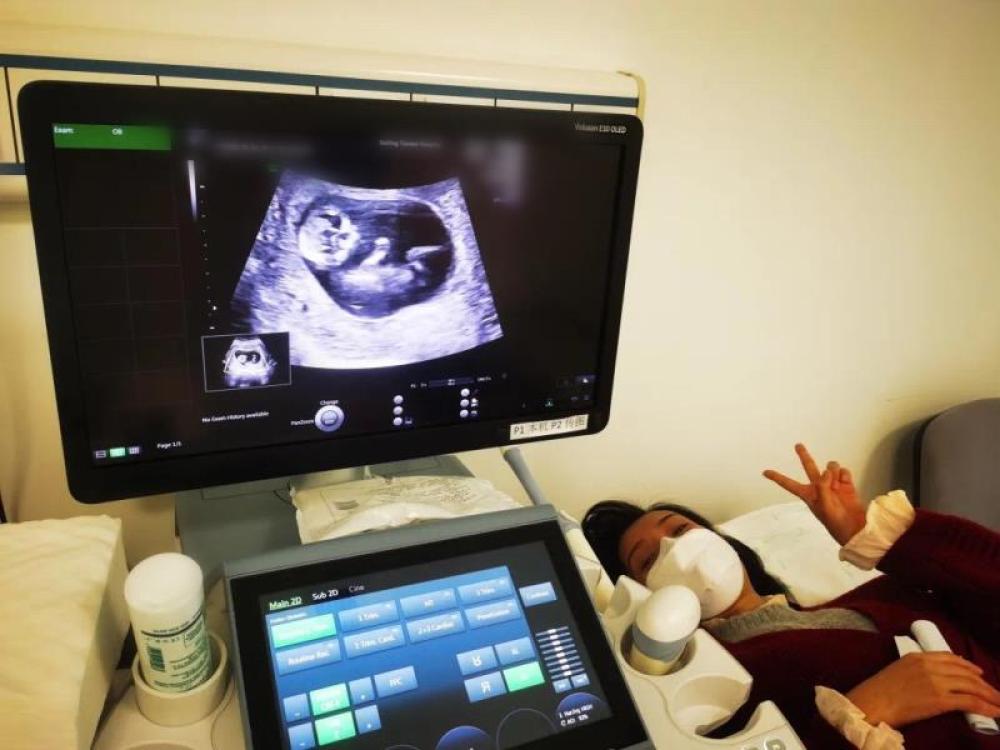

今天一早,妻子去(qu)醫院進行B超檢查,同事用手機拍攝下了B超顯示屏上的畫面,記錄下了這個87天的小家(jia)伙第一次“亮相(xiang)”。

圖為北京天壇醫院袁磊愛人做B超檢查。

“袁磊,看(kan)看(kan)你們家寶寶,可(ke)愛嗎(ma)?”收到(dao)同事發來的視(shi)頻,第(di)一眼就(jiu)看(kan)哭了,身邊的同事看(kan)完視(shi)頻也哭了。

視頻(pin)里(li),這個小家伙好(hao)像(xiang)聽到(dao)了外面的(de)召喚,在媽媽的(de)肚子(zi)里(li)伸手、踢(ti)腿、翻(fan)身,用各種動作(zuo)進行回應……看到(dao)他那小胳膊小腿,一種從未有過的(de)幸福感不(bu)停地向(xiang)上(shang)涌,眼(yan)淚怎么也控制不(bu)住。

其實在武漢這么多(duo)天(tian),他一直就是我(wo)的牽掛,今天(tian)終于看到他了,那種感受真(zhen)是又(you)緊(jin)張又(you)激(ji)動,雖然還看不(bu)清他的樣子,但(dan)是已經(jing)感受到他的活力。